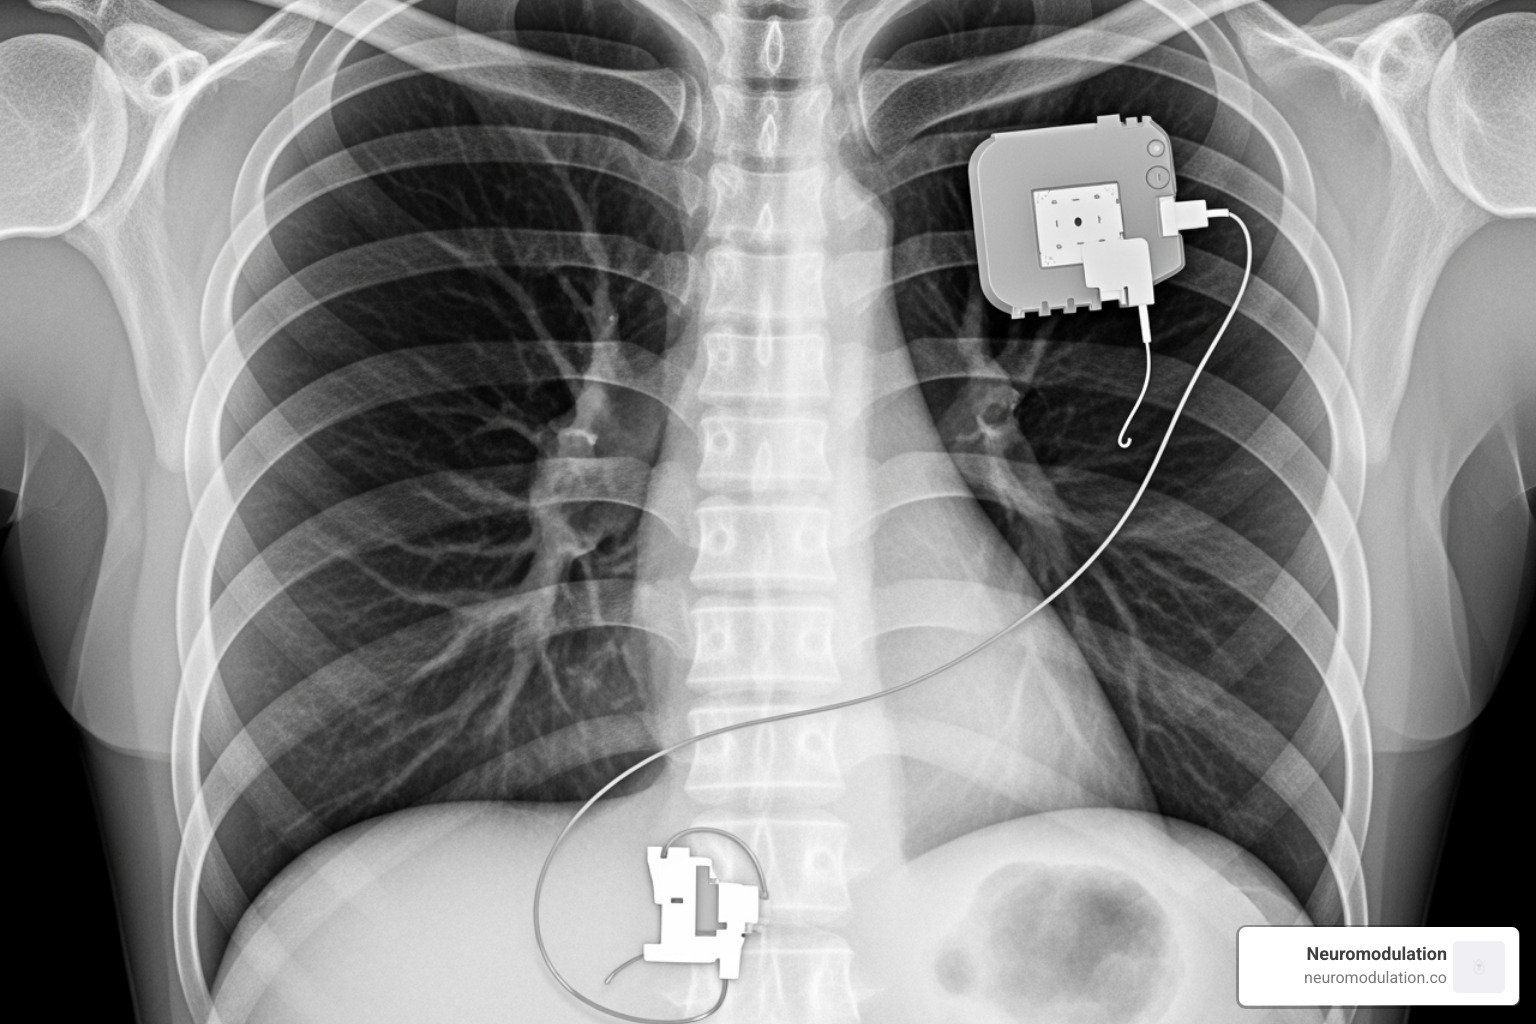

When your radiologist examines your chest X-ray, they’re essentially reading a roadmap of your new HNS system. Each component has its own distinctive signature on the image, like familiar landmarks on a well-traveled route.

The star of the show is your Implantable Pulse Generator (IPG) – the brain of your entire system. On your X-ray, it appears as a bright white, rectangular device sitting comfortably in your right upper chest wall. Your surgeon tucked it right under the skin, usually nestled over your pectoralis muscle.

Why the right side? It keeps the device away from your heart’s electrical activity and gives the cleanest signal possible. The IPG is roughly the size of a large coin, so while you might feel it under your skin initially, most patients forget it’s even there within a few weeks.

Next, we follow the respiratory sensing lead as it travels from your IPG down toward your lower chest. This thin, wire-like structure shows up as a delicate curved line on your X-ray, extending into the space between your ribs (called the intercostal space).

This clever little lead has one job: monitoring your breathing patterns by detecting when your diaphragm moves. Every time you take a breath, it sends a signal back to the IPG saying “now’s the time to stimulate!” It’s like having a personal breathing coach that never takes a break.